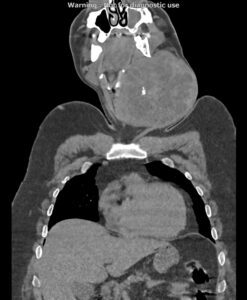

در سی تی اسکن اسپیرال از گردن ، ریه و مدیاستن با و بدون تزریق (مولتی دیدکتور 16 با مقاطع ظریف و بازسازی های ساژیتال و کرونال):

بیمار آقای 44 ساله با توده گردنی جهت بررسی بیشتر، مراجعه نمودند:

تصویر توده بزرگ به ابعاد 118x133mm در پلن آگزیال و دیامتر کرانیو کودال 126mm در سمت چپ گردن با نمای هتروژن و کلسیفیکاسیون Coarse مرکزی رویت می شود. به نظرمنشا توده ذکر شده از لوب چپ تیروئید می باشد. گسترش فوقانی توده تا سطح مهره دوم گردنی و زیر زاویه مندیبل و گسترش تحتانی آن تا ناحیه سوپراکلاویکولار بدون گسترش اینتراتوراسیک رویت می شود.

دو لنف آدنوپاتی سنترال چپ (zone 6) با حداکثر SAD=16mm مشهود است.

تعدادی لنف نود کوچک در زون های لترال دو طرف با ابعاد غیرپاتولوژیک مشهود است.

اثر فشاری توده ذکر شده به تراشه با انحراف آن به سمت مقابل رویت می شود.

اثر فشاری توده ذکر شده به ورید ژوگولارداخلی و CCA با جابه جایی خلفی و به SCM با جابه جایی خلفی لترال آن مشهود است.

مجموع یافته ها مطرح کننده توده تیروئید با اثرات ذکر شده می باشد.